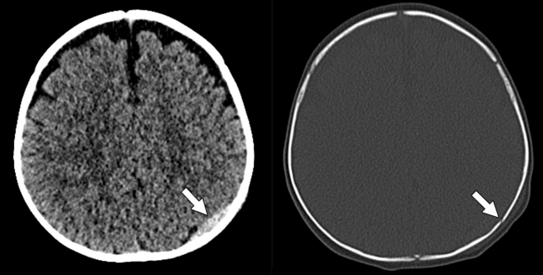

After Nancy A. Chauvin of Penn State Health Children’s Hospital in Hershey expertly examined pediatric arthritis, bone tumors, and bone marrow disorders, Strouse, senior author of the recent AJR Expert Panel Narrative Review on “Debunking Fringe Beliefs in Child Abuse Imaging,” explained how misattributing injuries leaves children at risk for future abuse (Fig. 2).

“Careful review of the scientific evidence and professional society consensus statements is important in differentiating findings attributable to child abuse from fringe beliefs used to discount the possibility that a child’s constellation of injuries is consistent with abuse,” Strouse maintained. He then listed the three categories that these fringe beliefs most often fall into: